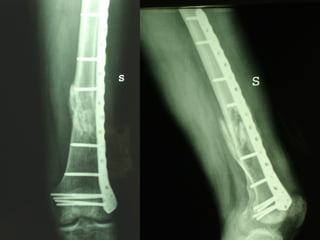

INDICAZIONI COMUNI Fratture sovracondiloidee Fratture intercondiliodee Fratture diafisarie distali PARTICOLARI Fratture con grave osteoporosi Fratture periprotesiche

VANTAGGI CHIRURGIA MININVASIVA Mini Open Inserimento della placca sottocutaneo per scivolamento Viti percutanee Preservazione dei tessuti molli Ridotto danno vascolare Rapida ripresa funzionale

F, 68 y

LISS  NCB

NCB

Conclusioni Riduzione  anatomica Minimo trauma chirurgico Corretto equilibrio fra elasticità e stabilità Precoce mobilizzazione